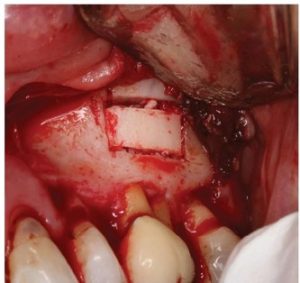

Bosworth Super-EBA was placed (Figure 11) and the root end burnished with a multi-fluted carbide bur. Radiographs were taken at the retro-preparation stage and the retro sealing stage to ensure accuracy of direction and material placement. The defect thoroughly debrided and was grafted with allograft (Straumonn Allograft) (Figure l 2). The cortical bone window was replaced and ensured to have no mobility (Figure 13)

The flap was closed with Ethicon 5-0 Prolene monofilament sutures (Figure 14) and a post-operative radiograph was taken (Figure 15).